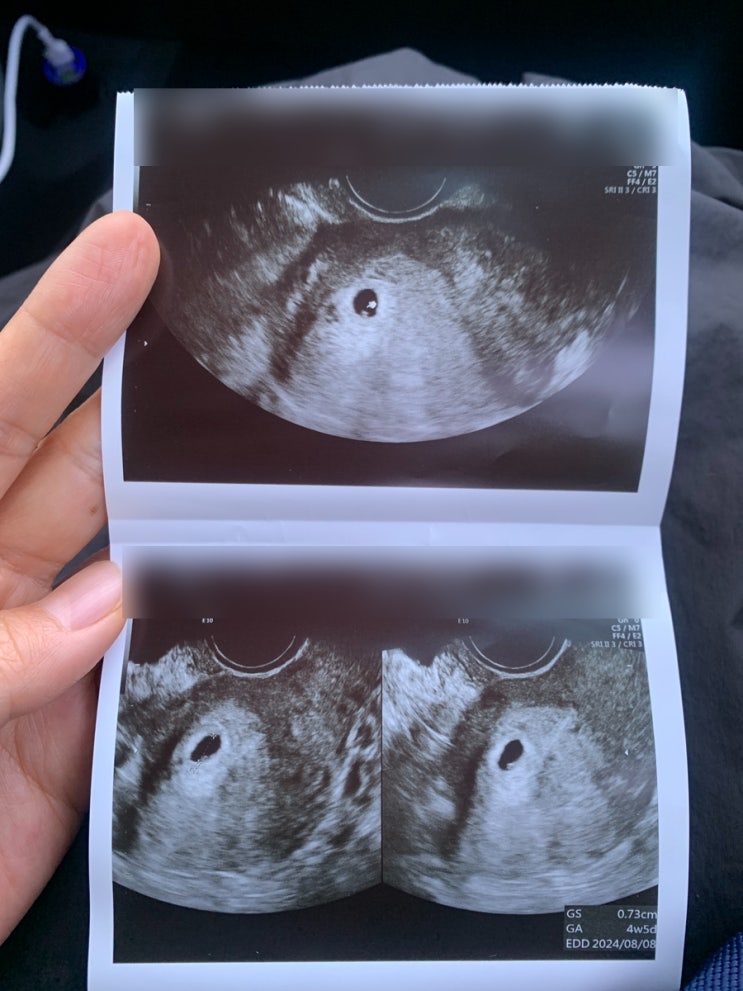

아기집 난황 확인과 난임 병원 졸업 : 임산부 식단과 일상

이어서 적는 지난 임신 일상 잘 먹고 잘 쉬었던 기록 찍어둔 사진들이 아까워서 지난 시간 기록하고 싶어서...